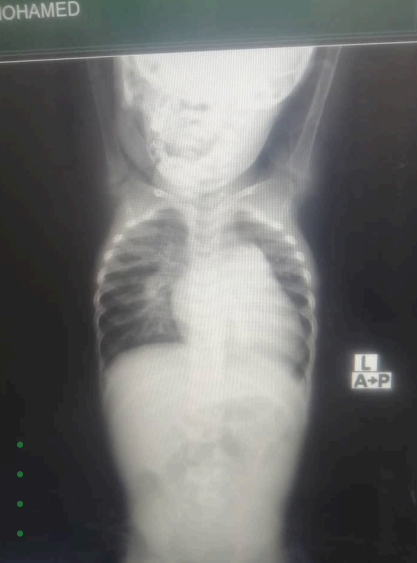

نجحنا في علاج طفلة كانت تعاني من ثقب في القلب، حيث خضعت لعملية جراحية بدولة مصر.